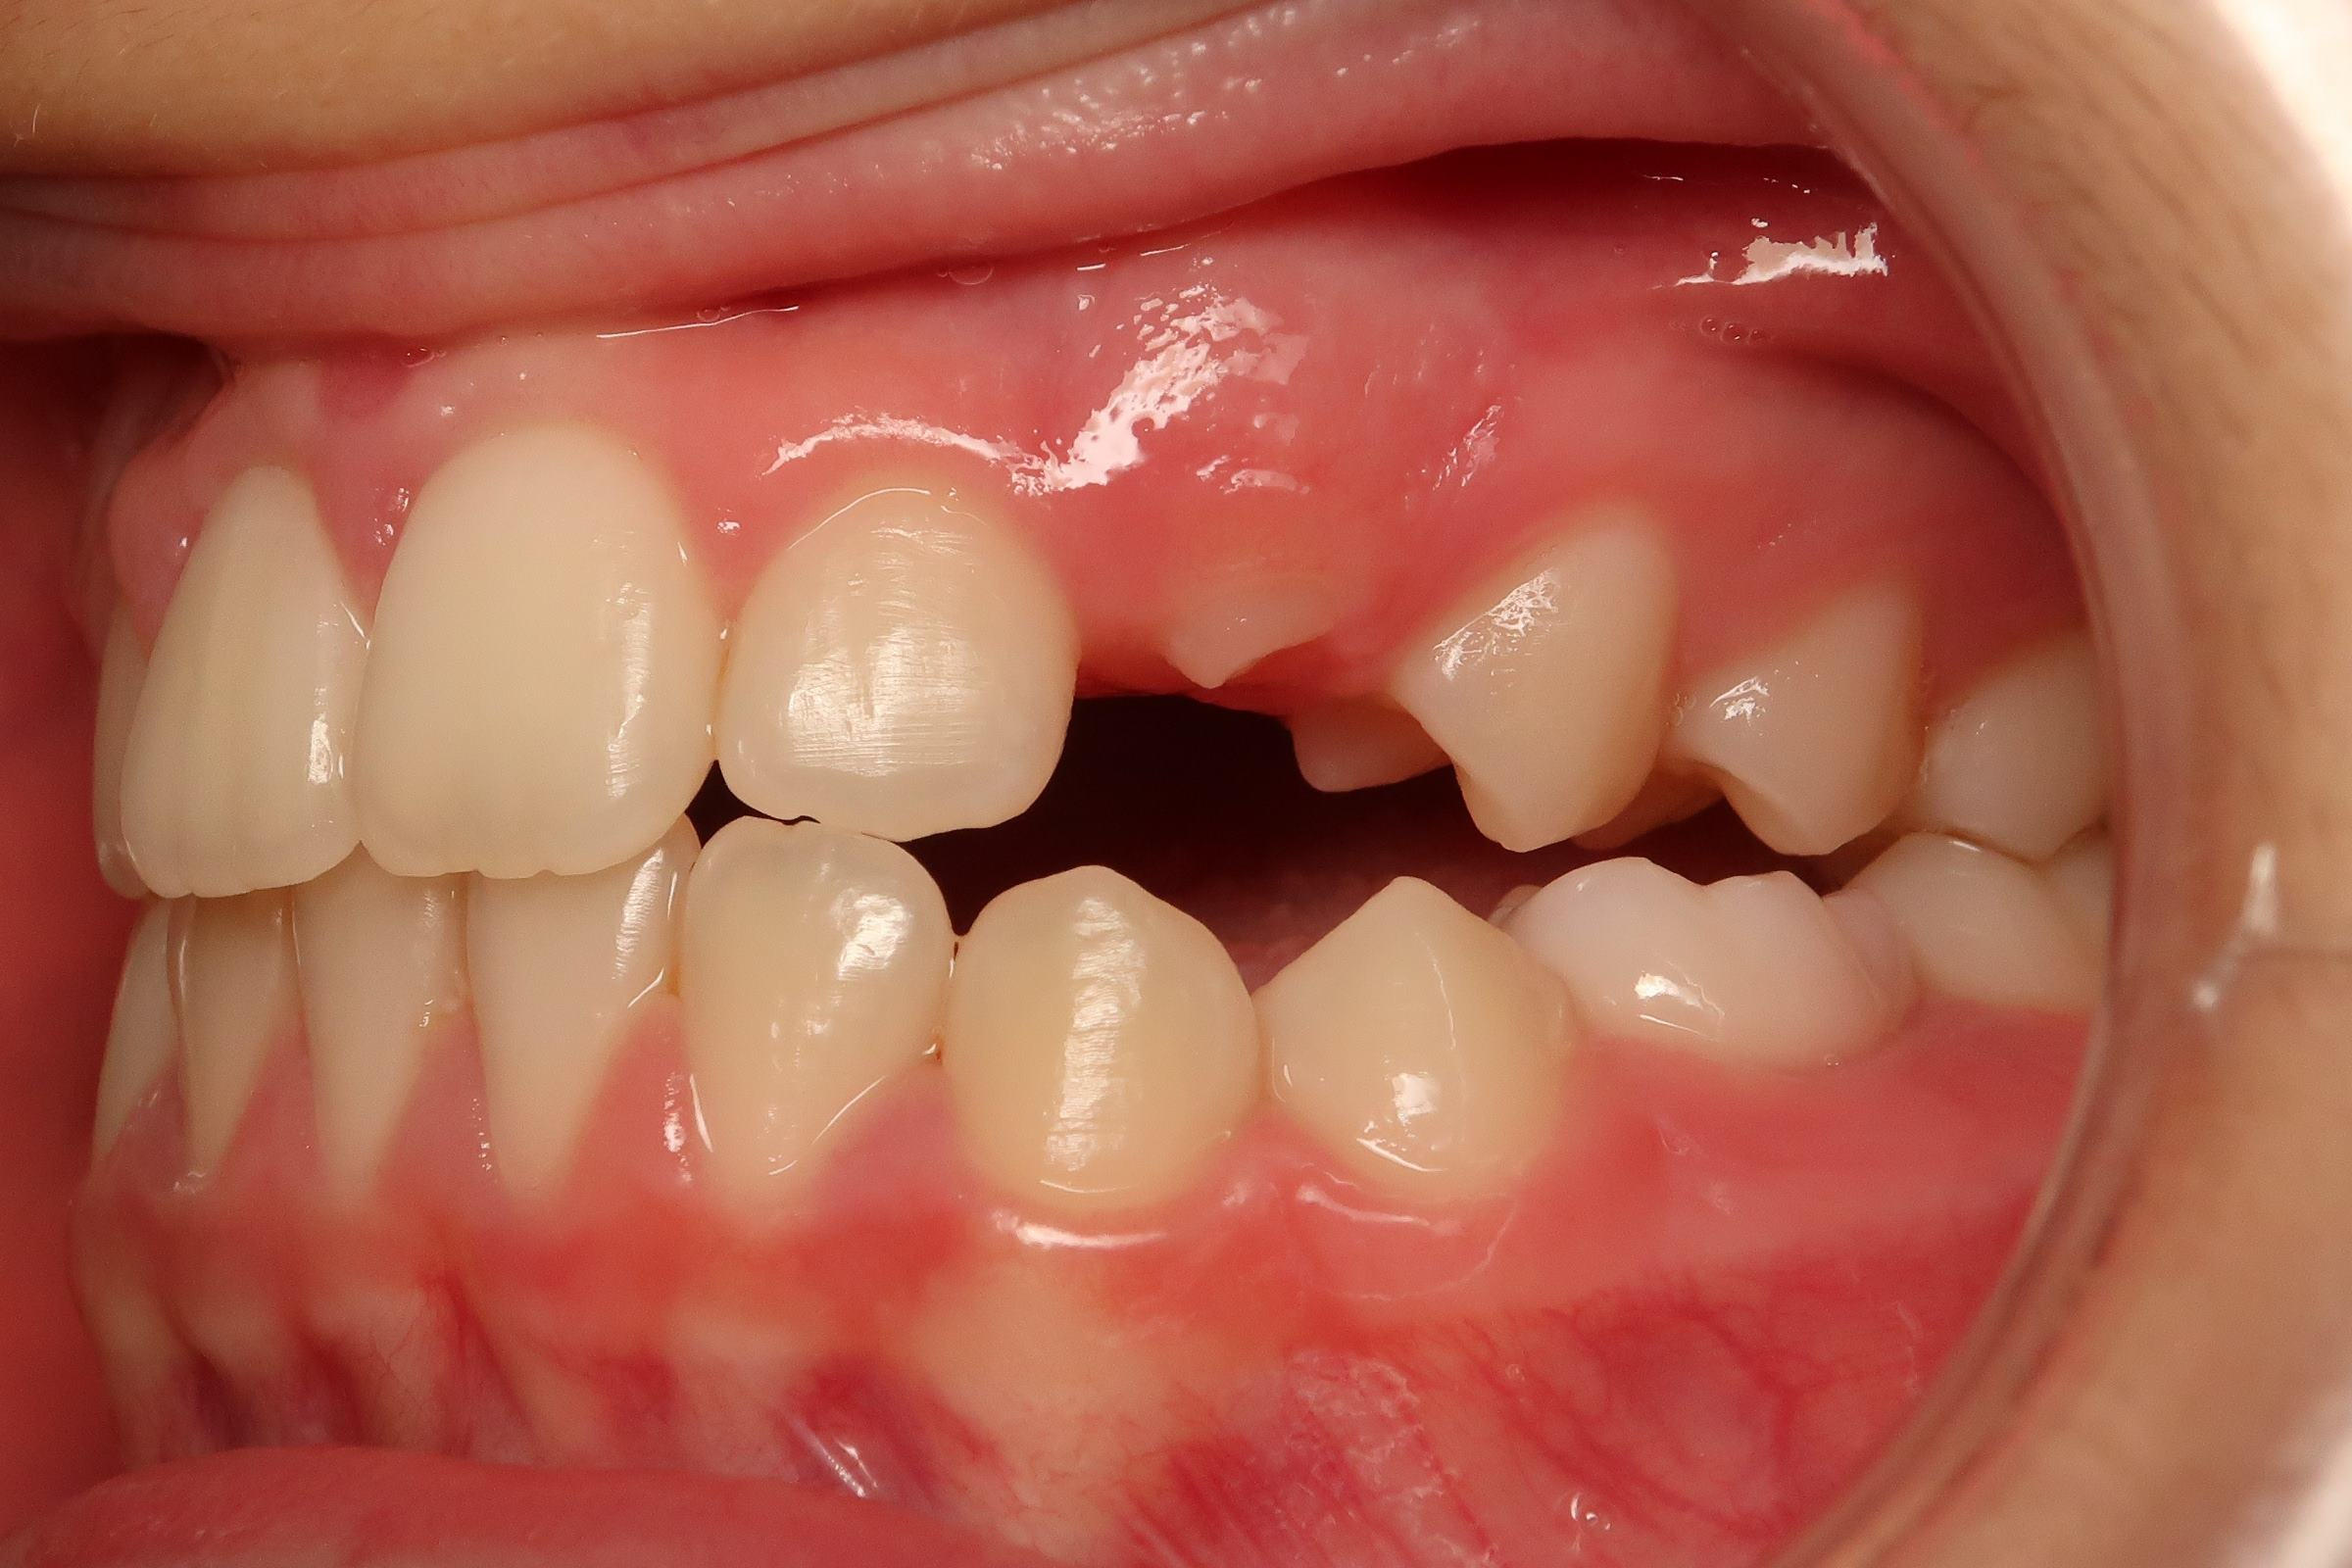

appareillage mobile pendant 22 mois

bilan début et en cours de traitement